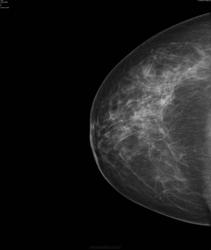

- https://radiomed.ru/sites/default/files/styles/case_slider_image/public/user/17752/bil6.jpg?itok=4aZB_8s6

Да, есть опухоль.. но пока небольшая

Слева опухолью Справа сгрукированые кальцинаты BIRADS 4 с двух сторон